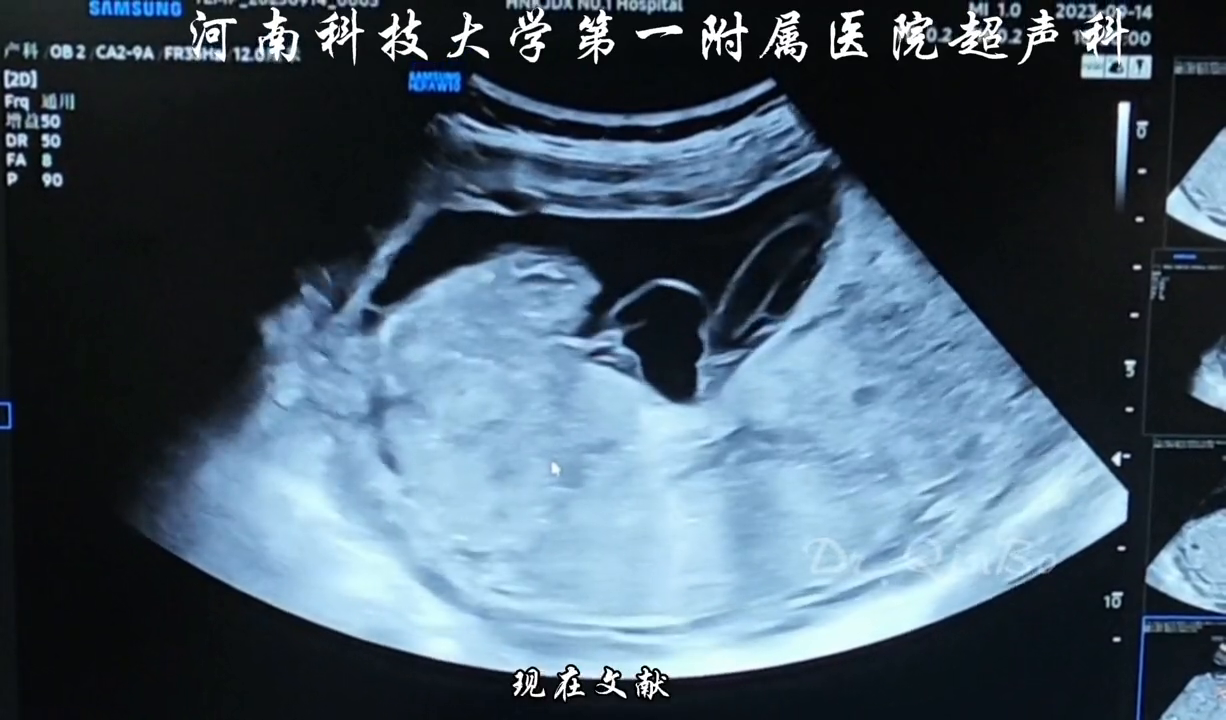

还有什么问题吗?脐带插入点也需要注意,正常的插入点应该位于胎盘中心部位或边缘。如果插入点位于胎膜上而非胎盘实质内,则称为翻状胎盘;如果插入点位于胎盘边缘,则称为球拍背胎盘。

拍片结果显示脐带插入点位于胎盘边缘,这种情况称为球拍背胎盘。如果插入点位于胎盘边缘且距离胎盘边缘一到两个公分处,则称为球拍状胎盘。